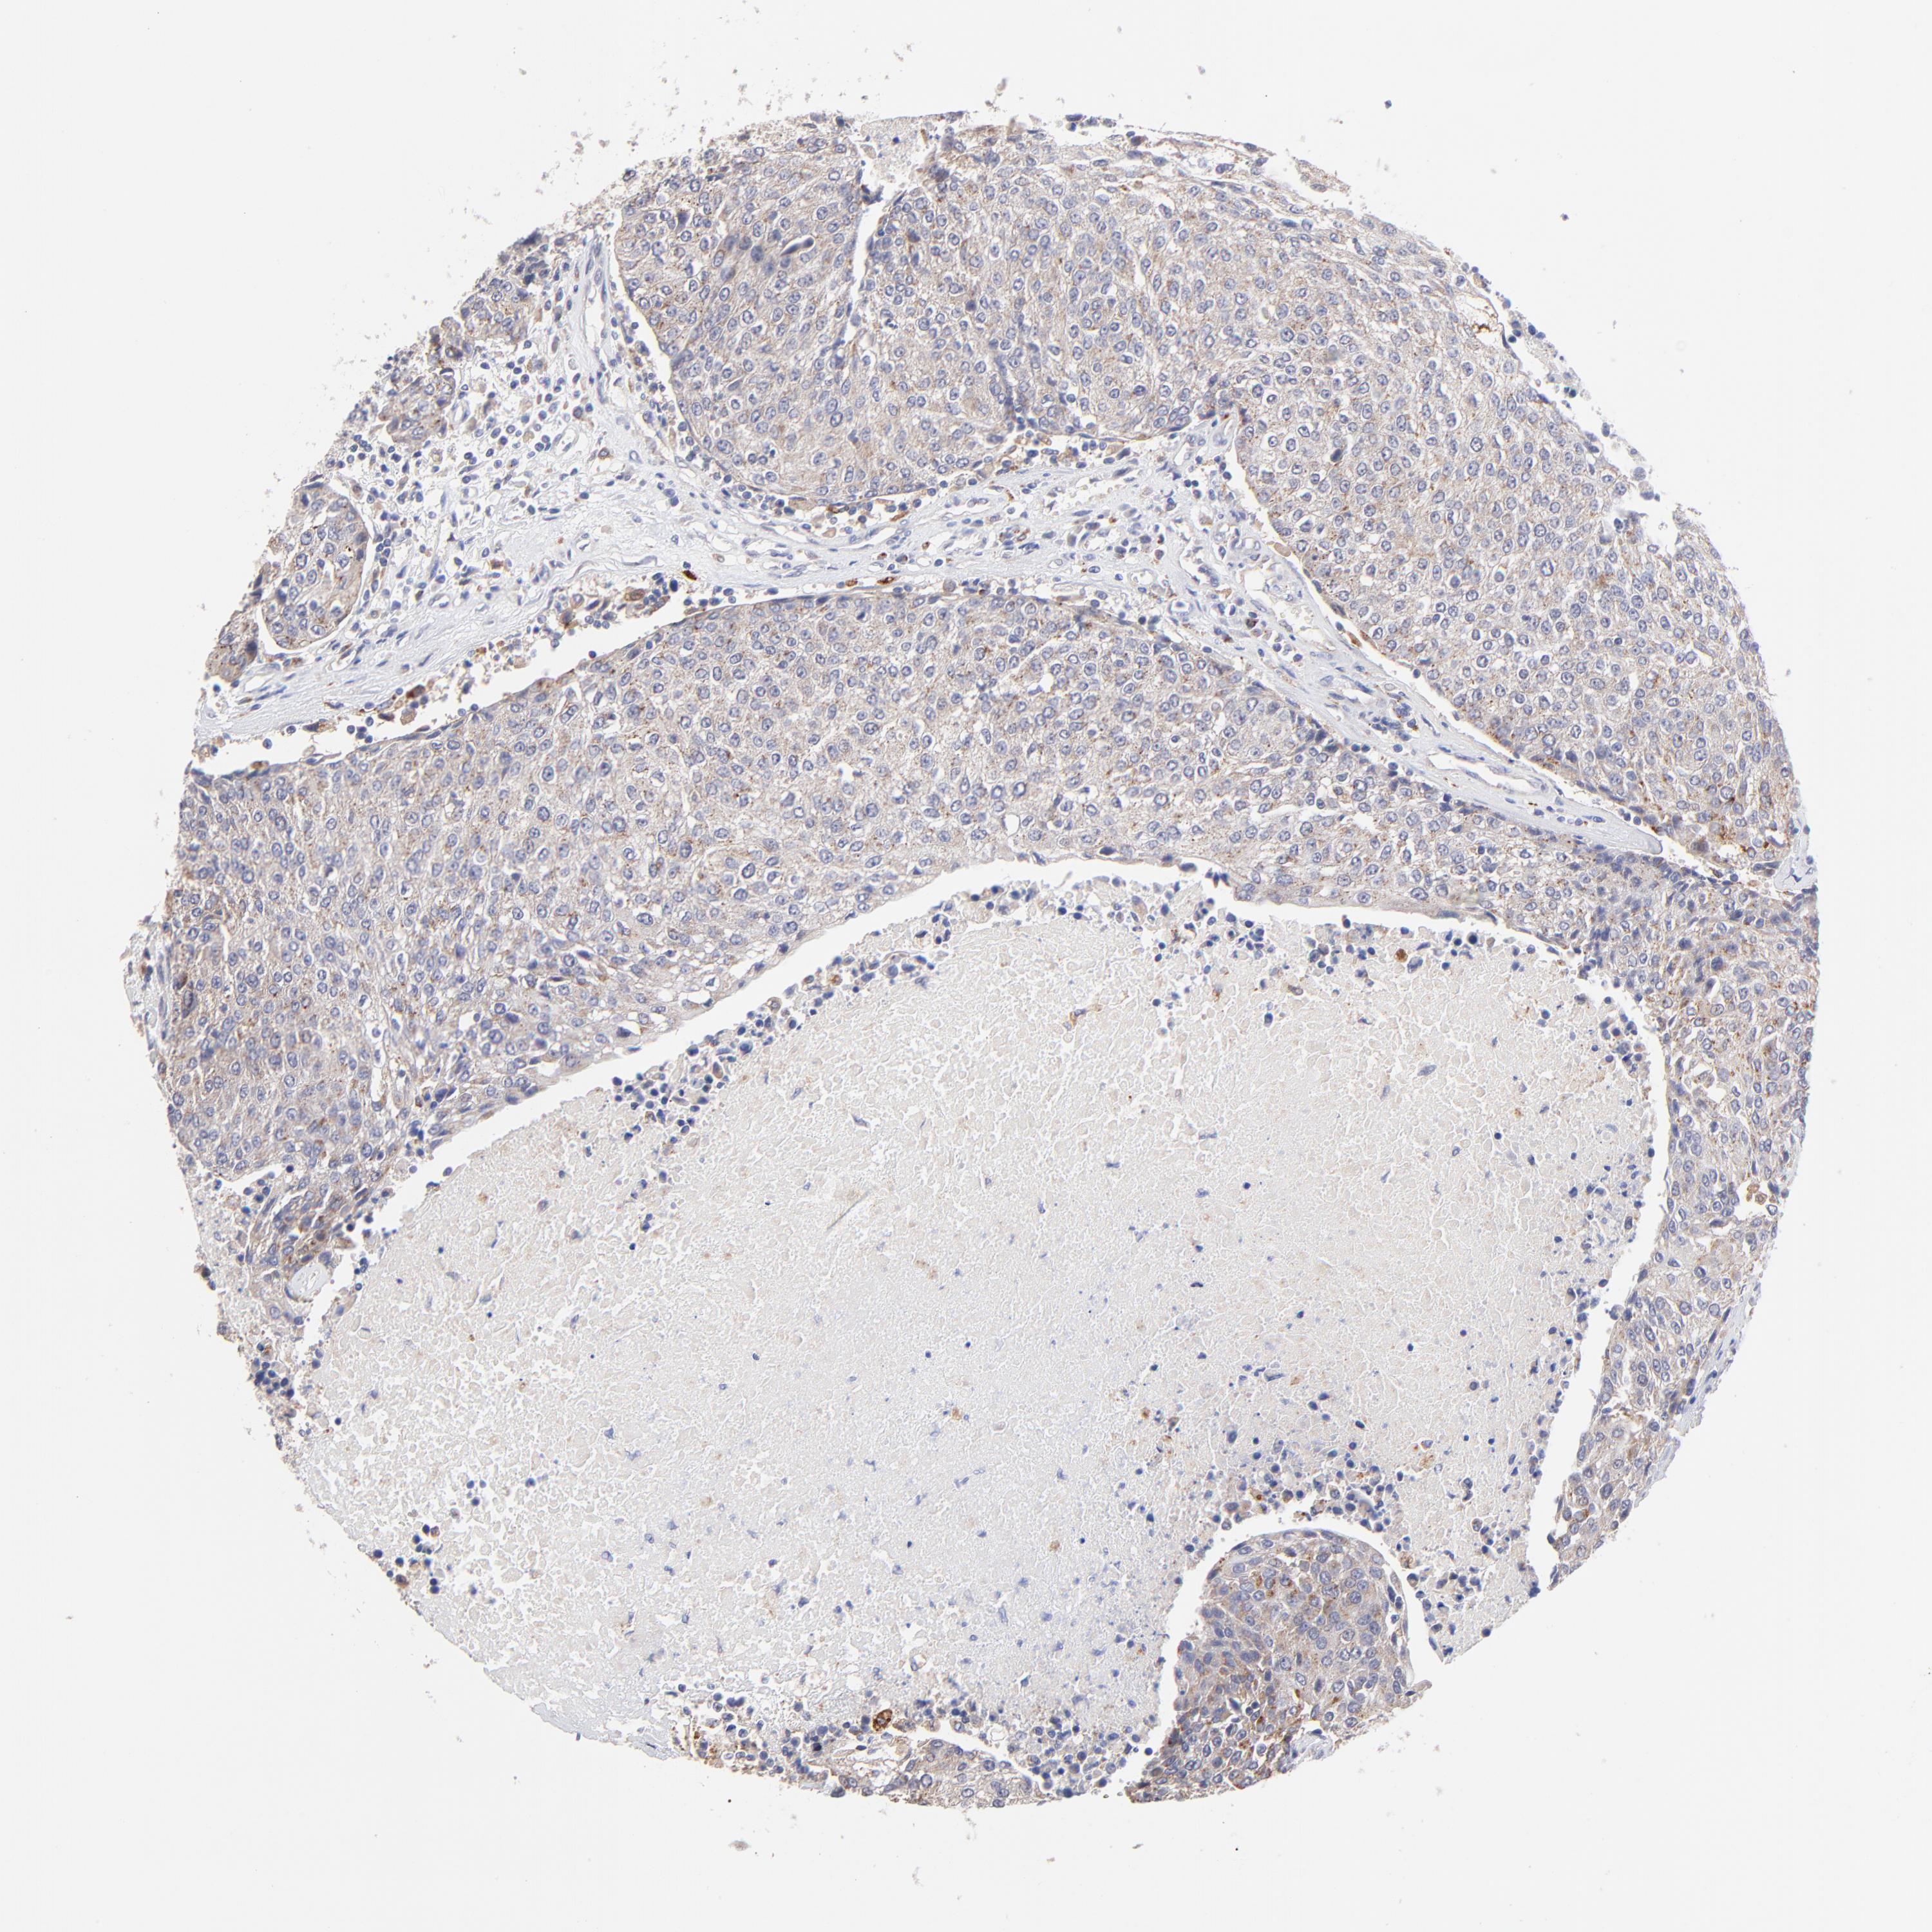

UROTHELIAL CANCER - Protein expressioni

A mouse-over function shows sample information and annotation data. Click on an image to view it in a full screen mode. Samples can be filtered based on level of antibody staining by selecting one or several of the following categories: high, medium, low and not detected. The assay and annotation is described here.

Note that samples used for immunohistochemistry by the Human Protein Atlas do not correspond to samples in the TCGA dataset.

Antibody stainingi

Antibody staining in the annotated cell types in the current human tissue is reported as not detected, low, medium, or high, based on conventional immunohistochemistry profiling in selected tissues. This score is based on the combination of the staining intensity and fraction of stained cells.

Each image is clickable and will lead to virtual microscopy that enables deeper exploration of all samples and also displays staining intensity scores, fraction scores and subcellular localization as well as patient and tissue information for each sample.

Antibody HPA003005

Staining

High

Medium

Low

Not detected

Intensity

Strong

Moderate

Weak

Negative

Quantity

>75%

75%-25%

<25%

None

Location

Nuclear

Cytoplasmic/membranous

Cytoplasmic/membranous,nuclear

Urothelial carcinoma, High grade

Urothelial carcinoma, Low grade